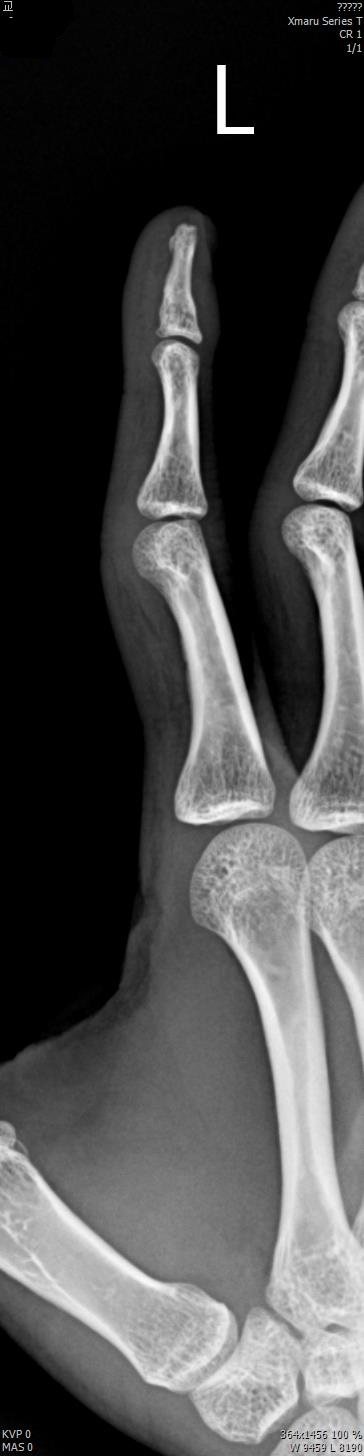

2017년 2월 14일 수지접합 ( 좌측 2수지 절단 치료 전, 후 모습)

2017년도 224일 당시 ( 외국인 교 **)께서 기계에 전달되어 본원 방문함.

올 해 19일 약 1년여간 수지접합 치료 전,후 과정을 올립니다.